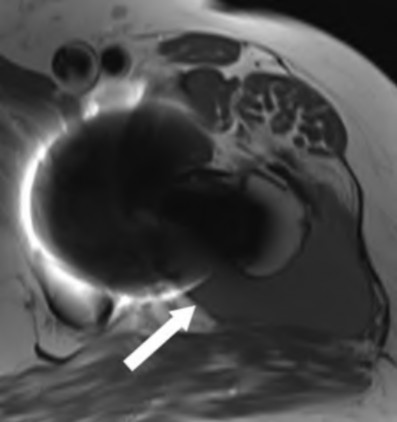

Question 43

A patient with a metal-on-polyethylene (MoP) THA presents 5 years postoperatively with sudden onset groin pain. Blood work reveals serum Cobalt levels significantly higher than Chromium levels. MRI with MARS sequencing shows a solid and cystic pseudotumor around the hip. What is the primary pathophysiologic mechanism for this failure?